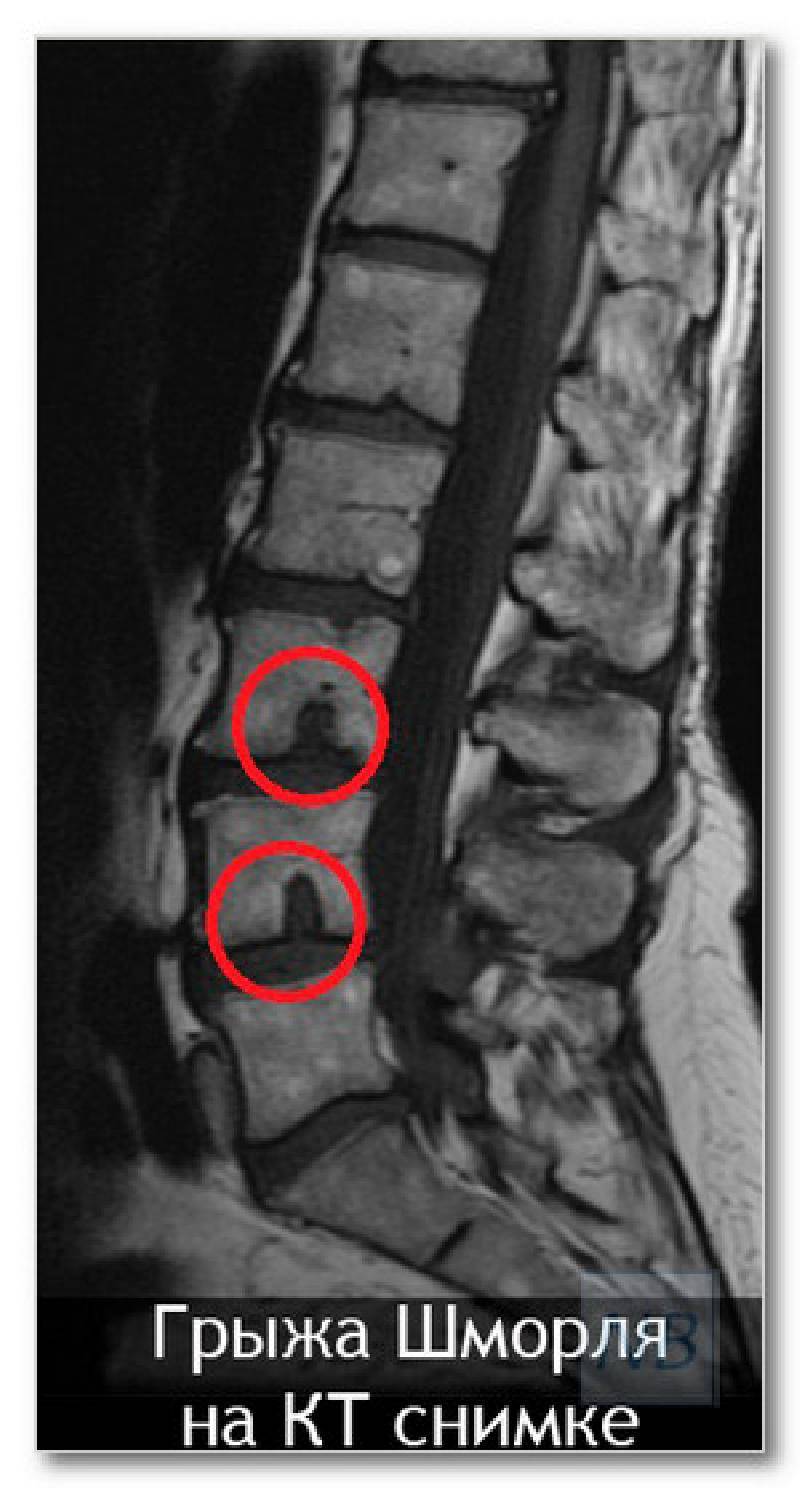

КТ-протрузии дисков: Визуализация и классификация